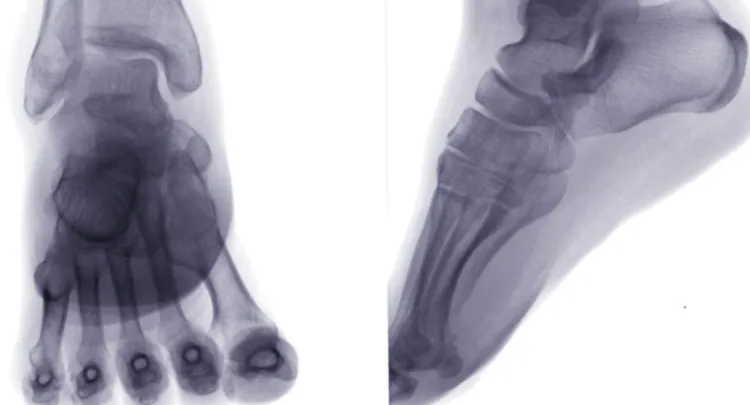

If you have concerns about your health, go to a reputable hospital's orthopedic or oncology department in a timely manner. Doctors will use examinations such as X-rays, CT scans, and MRI to make an assessment, ultimately relying on a pathological biopsy for a definitive diagnosis.